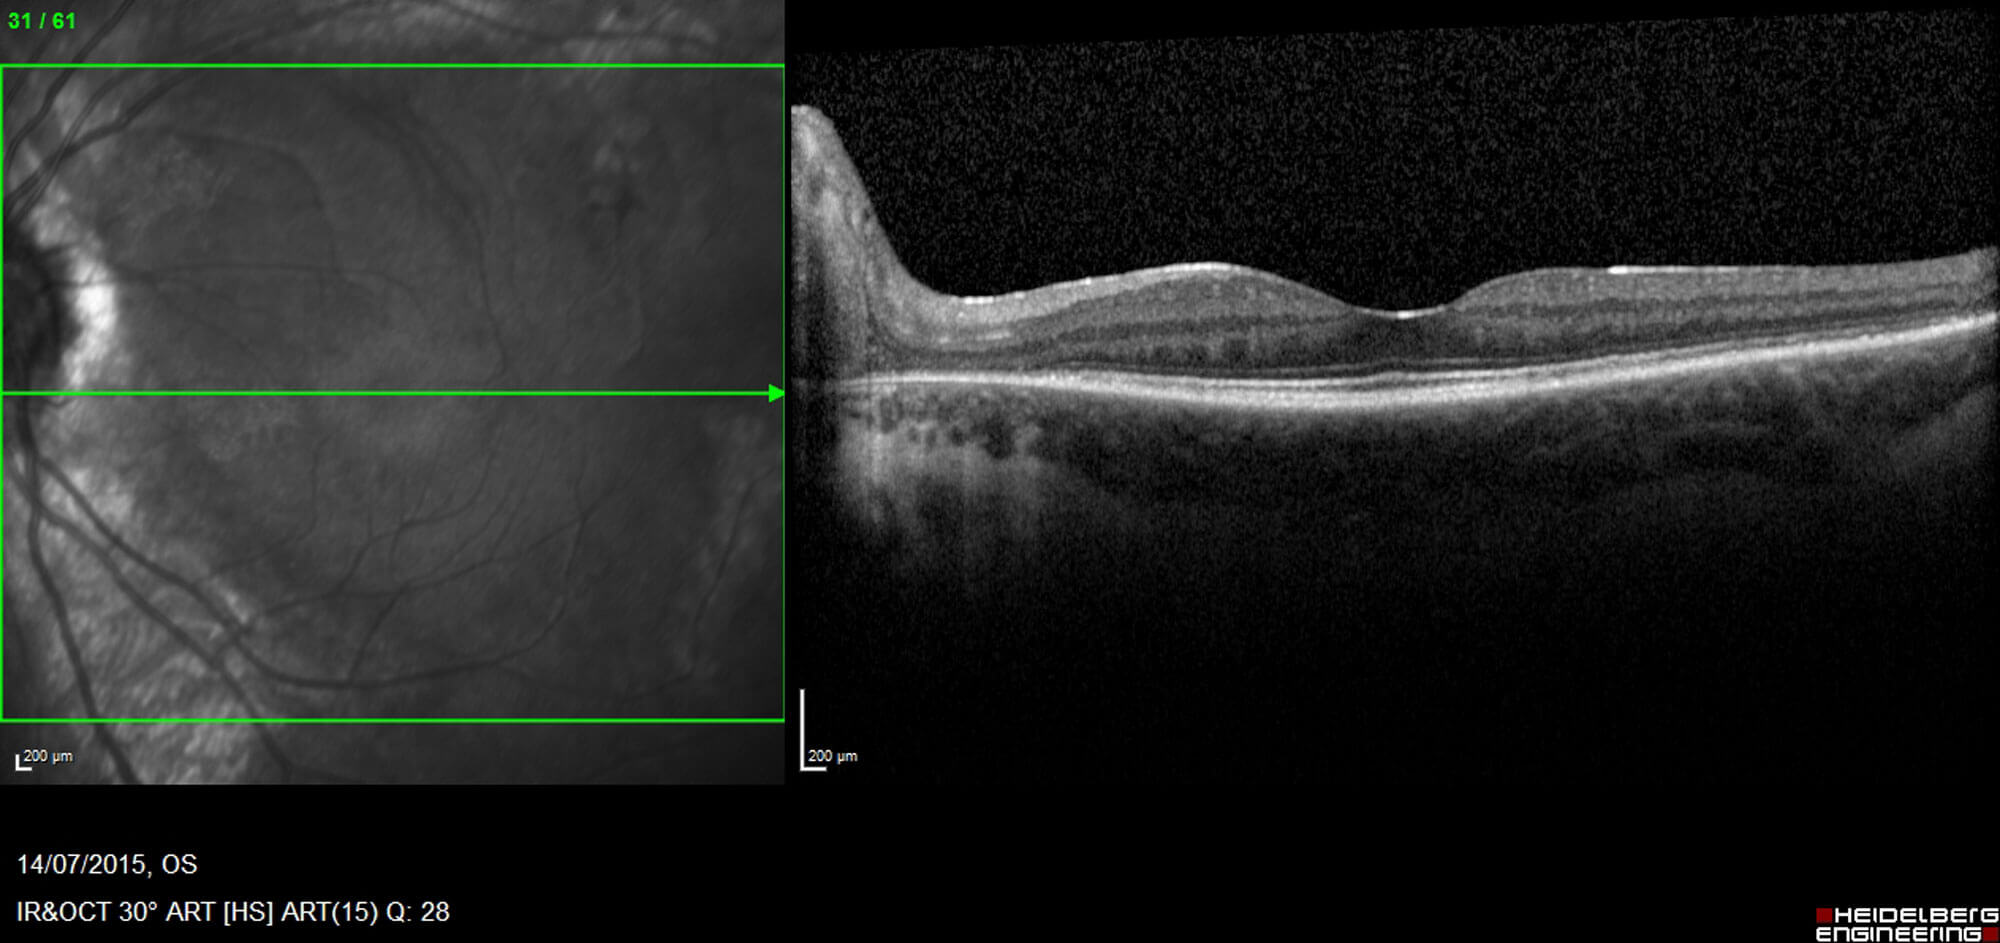

Figures 4a and 4b: Macula OCT demonstrating normal anatomy at the central macula and fovea.

Her fundus appearances remained largely unchanged over three years aside from a slight increase in pigment deposition within the same distribution. Her visual acuity remained excellent at 6/6 or better in both eyes at each visit. The visual field remained stable or only very slowly progressive. Macula OCT at each visit remained stable and dry.

In human eyes, descriptions of histopathological change are based on multimodal imaging techniques including spectral-domain-OCT (SD-OCT) and fluorescein angiography (FFA), as well as visual electrophysiology. In a retrospective study by Lee, et al., SD-OCT imaging of retinochoroidal atrophic areas in PPRCA showed thinning of the outer nuclear layer (ONL), external limiting membrane (ELM), ellipsoid zone (EZ) and interdigitation zone (IZ) band. Reduced choroidal thickness is another feature even in the absence of RPE atrophy. Pigmented paravenous retinochoroidal atrophy also appears to primarily affect choroidal vasculature as evidenced by findings in keeping with choriocapillaris hypoperfusion on OCT angiography, with relative sparing of the retinal capillary plexuses [12]. Macula may be involved and this is characterised by disruptions of the EZ, IZ, and RPE, as well as choroidal thinning [10,12].

Optical coherence tomography

Optical coherence tomography findings include absent EZ and ELM, thinning of ONL and outer plexiform layer, partial preservation of RPE, and choroidal thinning. Retinal nerve fibre layer and GCL can also be thin, and in cases with macular atrophy, thinning of all retinal layers may be present [17]. Pigment clumps appear as hyper-reflective plaques with underlying shadowing [15]. Optical coherence tomography angiography findings are characterised by vascular impairment, especially at the level of deep capillary plexus [17].